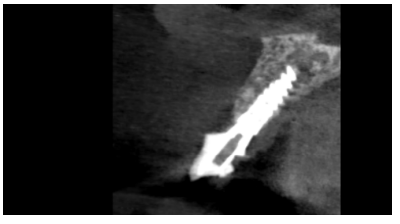

Caso clínico: Se presenta el caso de una paciente mujer de 32 años de edad, que acude por presentar una posible fractura radicular del incisivo central superior izquierdo (ICSI), acompañada de la aparición de un absceso periodontal en la región del fondo de vestíbulo de dicho diente. Tras llevar a cabo la exploración clínica y radiológica, se establece que el pronóstico del ICSI es desfavorable para llevar a cabo un tratamiento conservador del mismo. Tras la valoración de las características clínicas del caso presente, el plan de tratamiento se inclinó por la realización de la exodoncia del ICSI con la colocación simultánea de un IOI postextracción y la carga inmediata con una prótesis provisional del mismo.

Clinical case: We present the case of a 32-year-old female patient who presented with a possible root fracture of the upper left central incisor (ULCI), accompanied by the appearance of a periodontal abscess in the region of the bottom of the vestibule of said tooth. After carrying out the clinical and radiological examination, it is established that the ULCI prognosis is unfavourable for carrying out conservative treatment of the tooth. After assessing the clinical characteristics of the present case, the chosen treatment plan was to extract the ULCI with the simultaneous placement of a post-extraction osseointegrated implant (OII) and immediate loading of a provisional prosthesis on the implant.